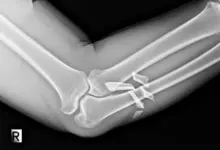

Casos Cirúrgicos: Quando a Intervenção se Torna Necessária

Em casos mais sérios, que não melhoram com tratamento comum, pode-se precisar de cirurgia.

A cirurgia busca melhorar a função do ombro e reduzir a dor de uma maneira mais efetiva, no entanto, os especialistas avaliam cuidadosamente o caso antes de decidir pela operação.

Após a cirurgia, é preciso seguir corretamente o pós-operatório, que inclui remédios, descanso, e fisioterapia. Assim, garante-se uma recuperação completa.